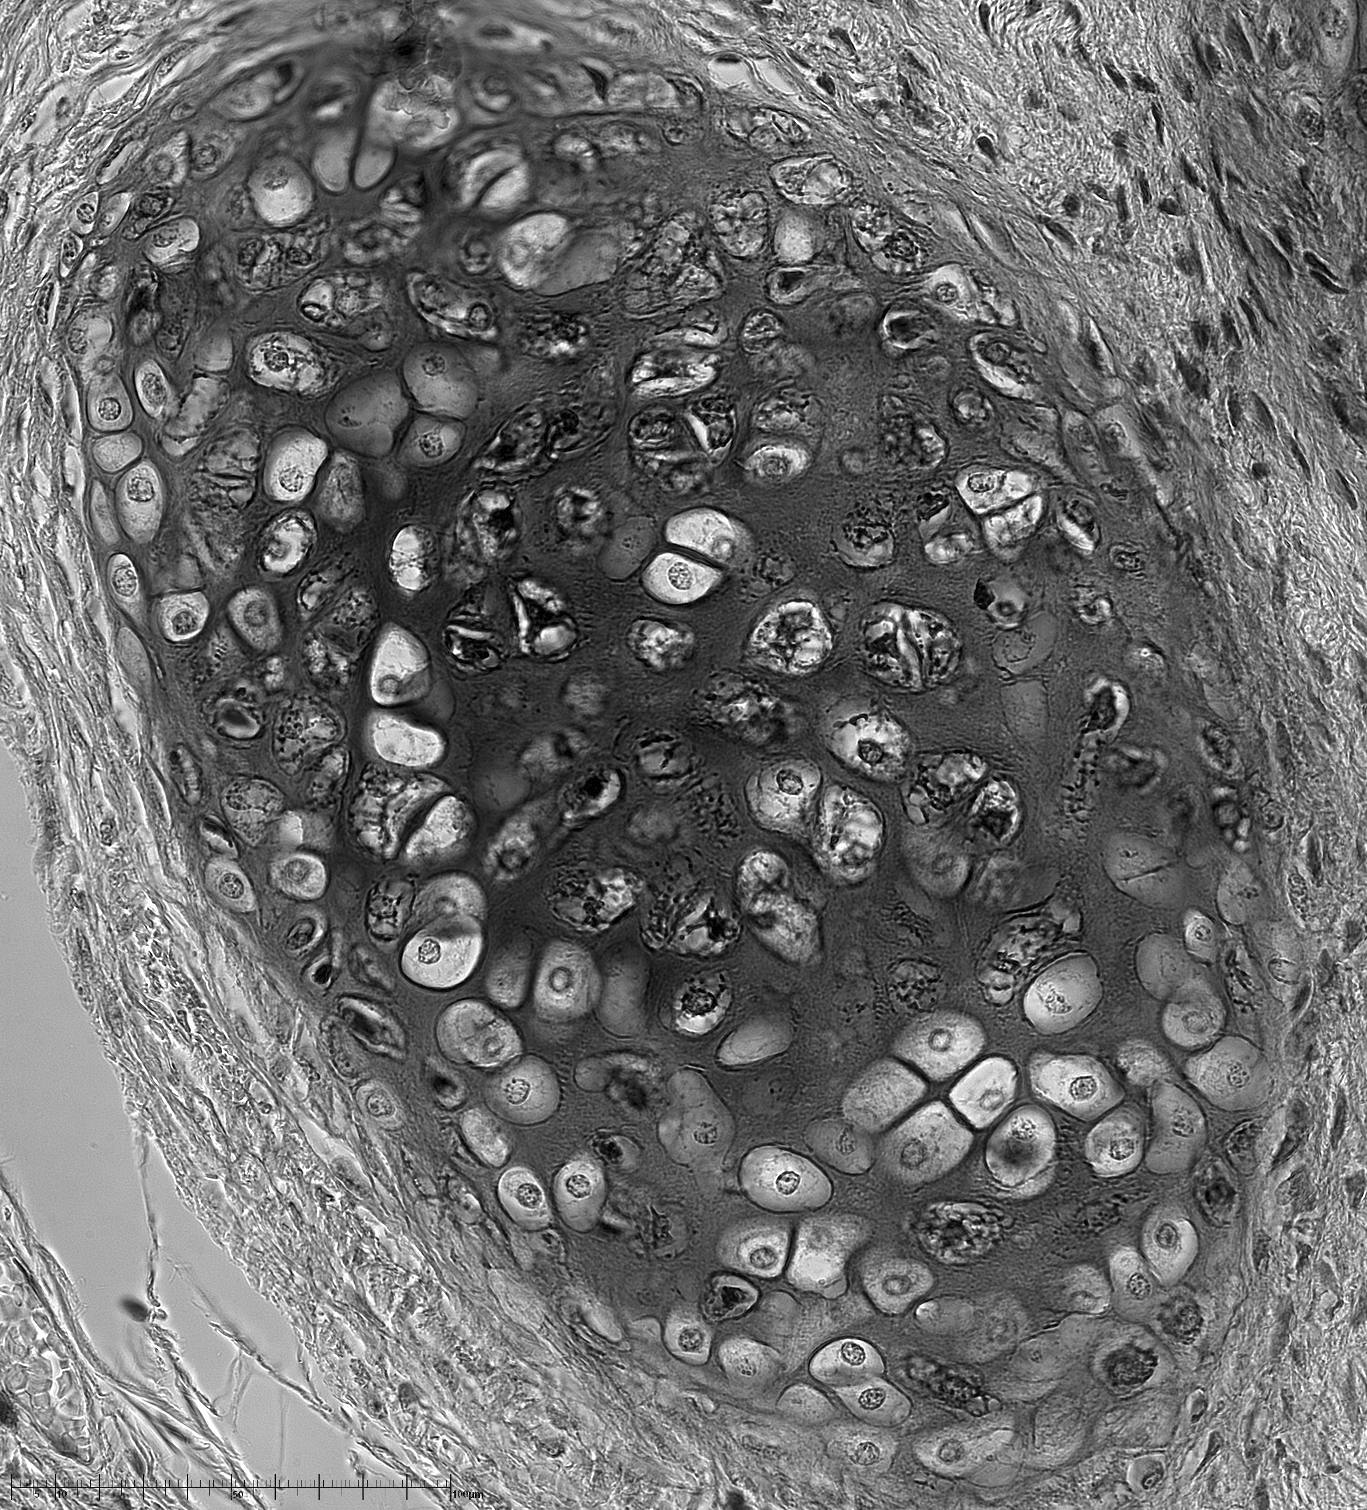

Si bien qu'en imagerie j'obtiens ceci avec l'objectif 40x, une barlow et une caméra (je n'utilise jamais le 100x, le grossissement est bien trop élevé et surtout il faut l'immerger dans une solution huileuse pour fonctionner).

image.thumb.png.471586356e694f9c7b8bf9afe4c53663.png

J'ai également une lame gravée avec une mire qui me permet d'obtenir la taille réelle. Elle est ici en bas à gauche, l'échelle totale est de 100µm, par graduations de 1µm.

On voit les noyaux de cellules humaines (c'est une lame d'un labo de biologie qui contient du tissu humain) qui font environ 5µm de diamètre dans la réalité.

L'image en taille réelle se trouve ici : http://www.astrosurf.com/colmic/Microscope/Tissu-humain-4x.jpg